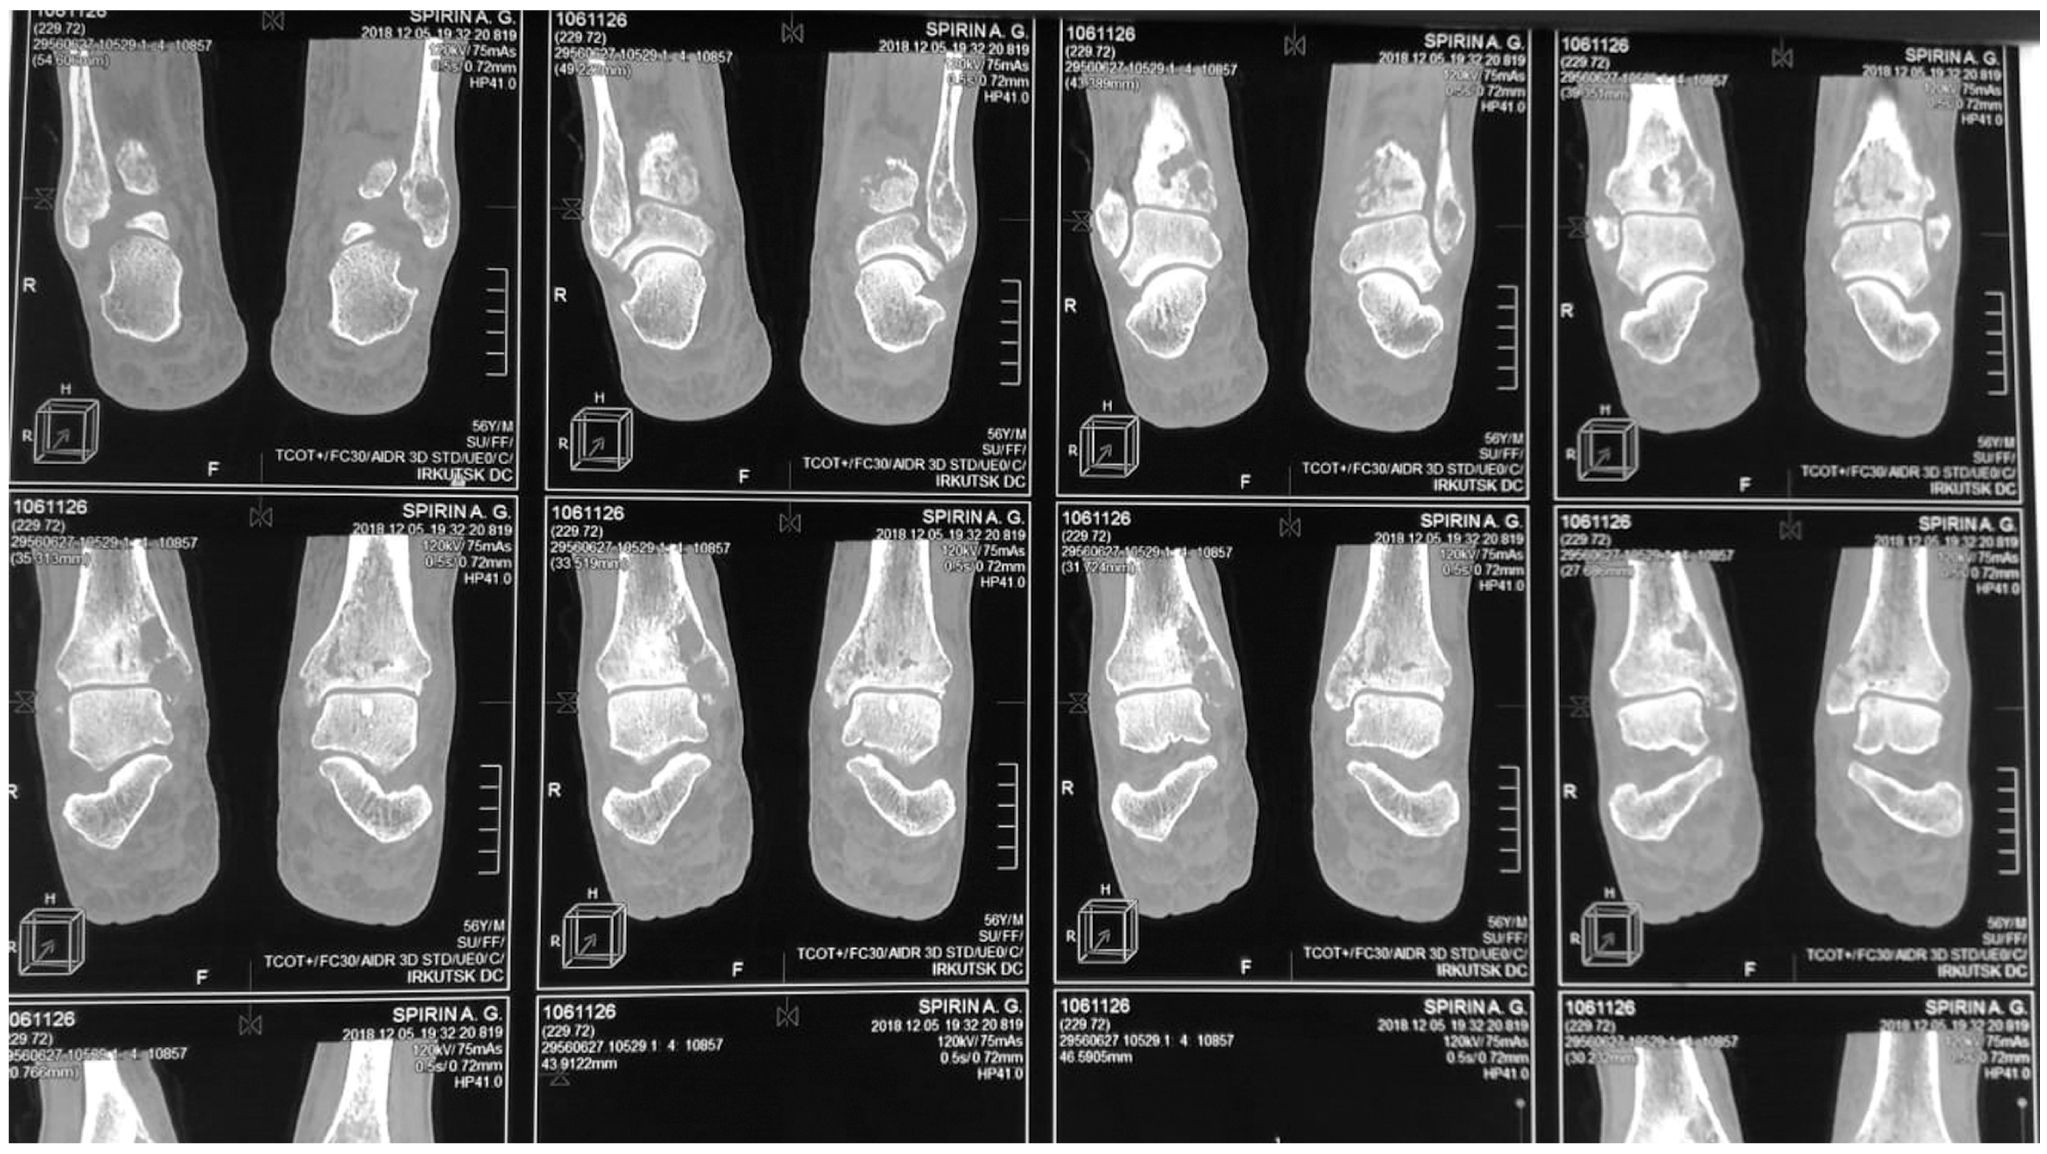

Instrumental examination. Multispiral computed tomography on 12.05.2019: cystic transformation, volume-occupying mass lesions and osteolysis in the distal areas of both tibial bones (Fig. 1). Chest cavity X-ray dated 16.05.2019: diffuse pneumosclerosis. Ultrasound examination of the abdominal cavity organs dated 20.05.2019: no signs of structural abnormalities.

Fig. 1. Multispiral computed tomography: osteolytic destructive changes in the distal areas of the tibial bones.